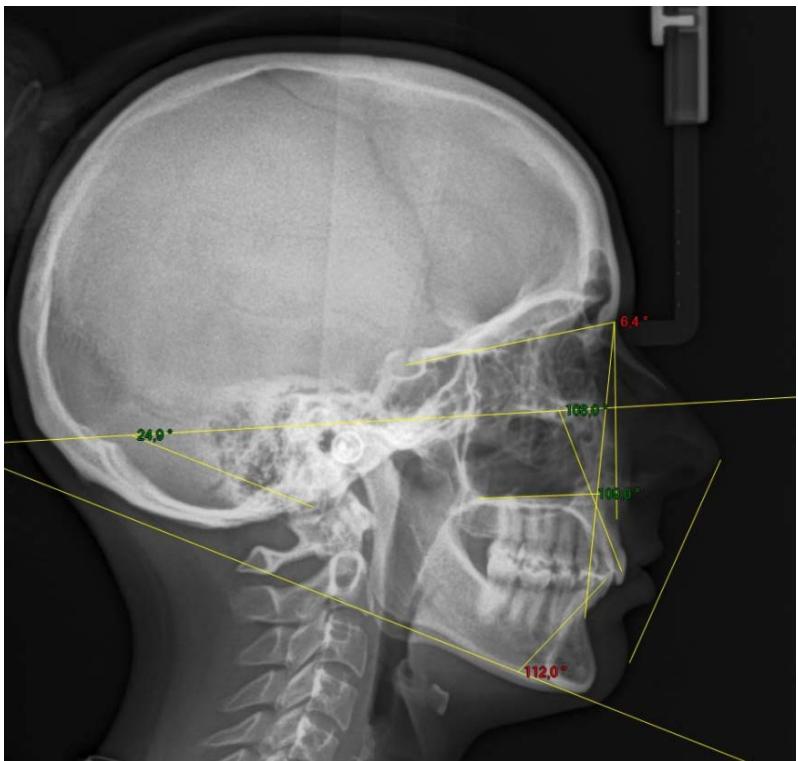

L'examen cephalométrique confirme le diagnostic de classe II squelettique par rétromandibulie et la forte vestibulo-version des incisives mandibulaires $(112^{\circ})$.

Examen cephalométrique de début de traitement.